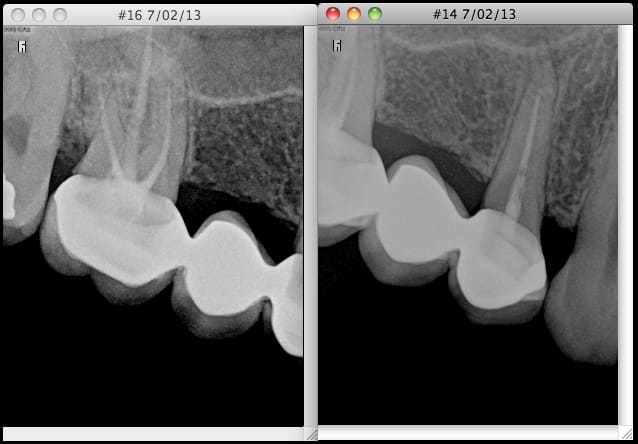

Il y a 5 ans, 15 extraite car fracturée.

Elle me certifie (en cours de vérification) que les 14 et 16 étaient vivantes et non cariées (peut être restaurées) et saines à ce moment là, ce qui est plutôt probable car mis à part un couronne sur 26 que je lui ai faite la seule prothèse est une 11 suite à un soleil en vélo quand elle était gamine. Sinon reste de la bouche = quelques amalgames peu volumineux.

La dentiste extraie donc 15 (normal) et hop bridge 14-(15)-16.

Résultat : Endos + bridge à reprendre à terme, joint dento-prothétique sur 14 plus que douteux (suspicion de reprise de carie sur l'ancrage fibré de 14).

anatomie radiculaires pas vraiment simples...les endos sont peut être pas top, mais rien ne dit que tu pourras faire mieux...

en effet la 14 semble avoir une reprise de carie...je ne sais pas trop ce qu'il va rester après éviction carieuse complète

donc, amha il faut déposer et évaluer que qui peut être fait/conservé et au moins reprendre le ttm de la 16...

instrument fracturé en prime dans la 16.

La 16 est-elle symptomatique ?

Sinon, tu ferais aussi bien de ne pas toucher amha : la radio ne montre pas clairement un foyer, et donc même si l'endo est mal compactée, et pas à l'apex, tu as assez de grain à moudre. Une endo radiologiquement contestable ne signifie en aucun cas une infection à traiter en urgence ; si la dent était saine quand elle a été dévitalisée, et correctement irrigué, il se peut qu'elle se tienne des années ("quand on voit ce qu'on voit"...)

Par contre je suis d'accord qu'une fois le tenon déposé sur la 14 il risque de ne pas y avoir grand chose à sauver... et je me demande ce qu'il y a sous la 16 ... alors ... plusieurs implants? PAP?

Et oui la 16 en MV c'est chaud... mais pas intentable avec une bonne cavité d'accès et la 14 est améliorable à mon avis.

Hé, y a pas une rhizalyse dans la 14?

Trés sincèrement , pour les endos j'ai largement vu pire ( en dehors une sous obturation et d'un élargissement desmontal , je ne vois rien) .

Radiologiquement , le bridge n'a pas l'air trop mal fait non plus .